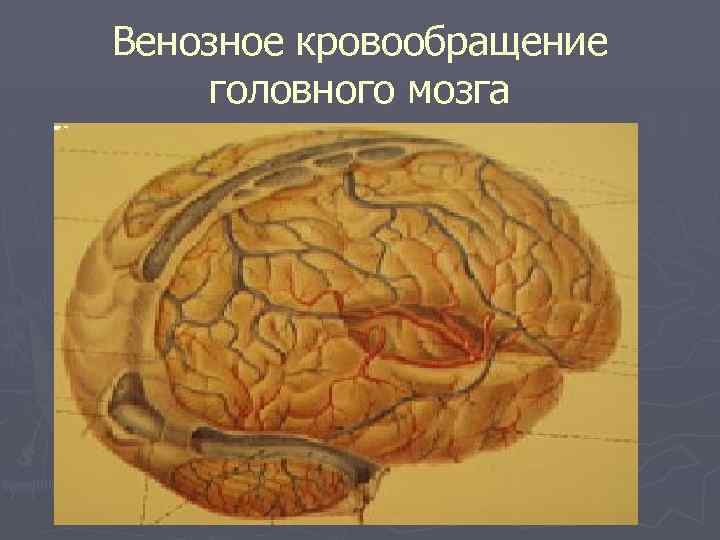

Венозное кровообращение головного мозга

Острые нарушения венозного кровообращения ► 1. Венозное кровотечение ► 2. Тромбоз вен мозга -асептический тромбоз -септический тромбофлебит